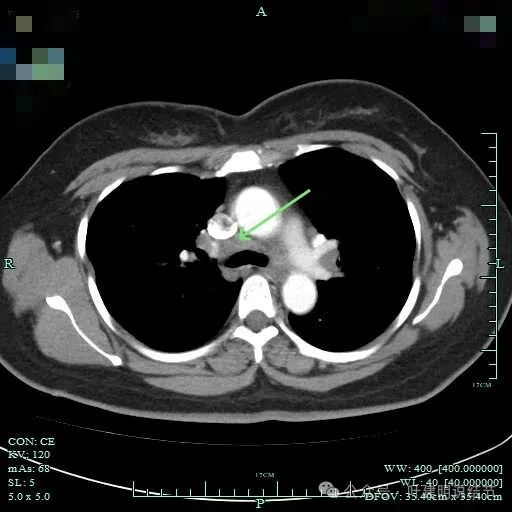

病灶纵隔窗上是软组织影,表面不平,形态不规则。上腔静脉旁有肿大淋巴结。

灶边部分细支气管扩张,腔静脉旁淋巴结较大

病灶有血管与之相连,淋巴结更显得明显了。

肺窗上见与上腔静脉紧贴着,病灶边缘稍显模糊。